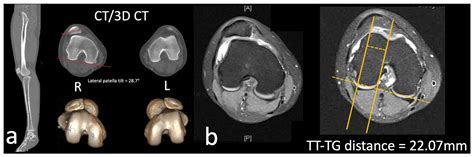

• lateral patellar tilt angle

• lateral patellar tilt and subluxation

• lateral patellar tilt radiopaedia